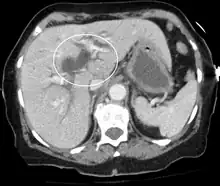

![]() | |

| Jaundice of the skin caused by pancreatic cancer | |

Medical imaging such as ultrasound, CT scan, and HIDA scan are useful for detecting bile-duct blockage.[40]